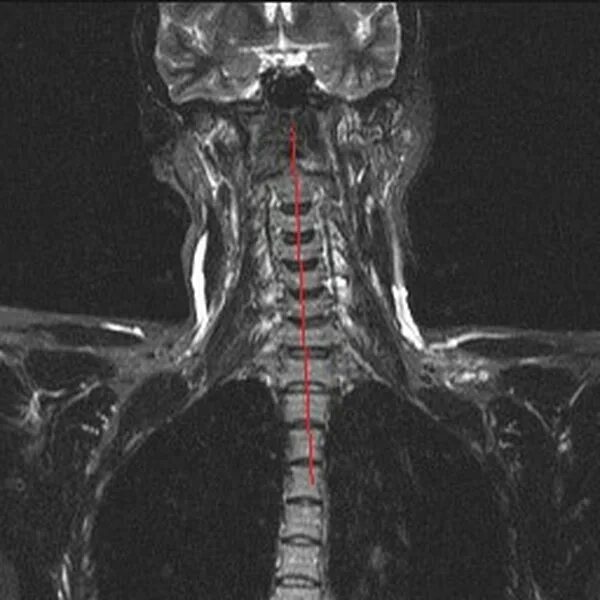

В шейном отделе мрт